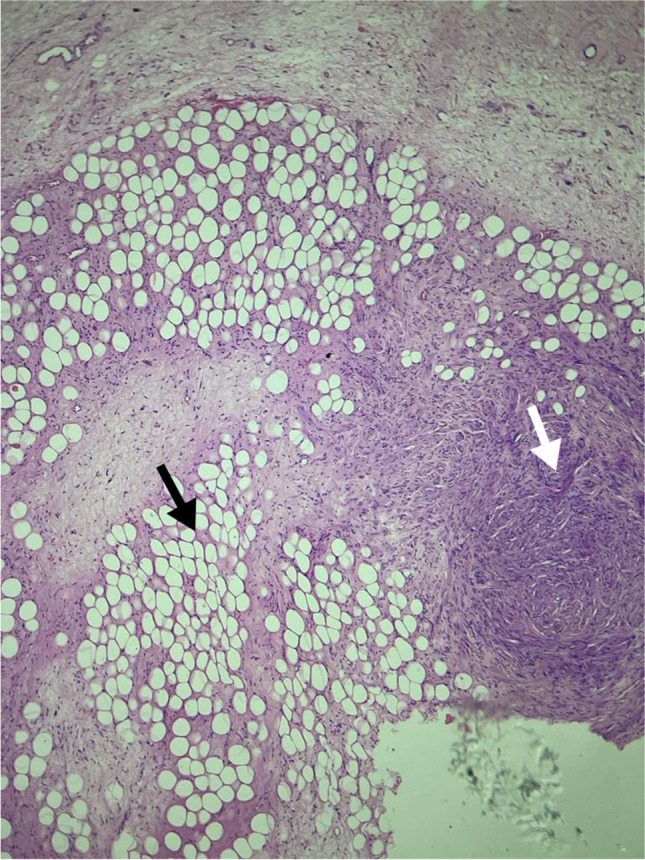

The postoperative biopsy report was suggestive of well-differentiated liposarcoma. The immunohistochemistry report came as lipoleiomyosarcoma. The histological images are shown in Fig. 4.

Fig. 4.

Histopathological image of lipoleiomyosarcoma. White arrow shows leiomyosarcomatous component. Black arrow shows lipomatous component of the tumor